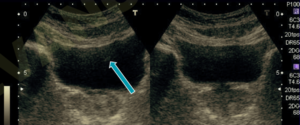

L’ANISOTROPIA e’ un artefatto che puo’ simulare una lesione.

Rappresenta la più comune causa di errore di interpretazione in ecografia muscolo-tendinea.

Essa si verifica quando il fascio di ultrasuoni non è perpendicolare al tendine. In questa circostanza il tendine o una parte di esso, normalmente iperecogeno, diventa anecogeno, simulando una lesione. In questo caso un valutatore con un pò di esperienza sa bene che basta variare l’angolo di incidenza per definire meglio l’area sospetta.

In realta’, durante la valutazione, sono eseguite anche scansioni ortogonali a conferma di lesioni sospette, pertanto in linea generale, NON E’ CONVENIENTE affidarsi ad una singola scansione senza avere la conferma della lesione anche in scansioni tra loro ortogonali e da differenti angolazioni. Solo in questo modo la valutazione puo’ essere certa e puoi essere SICURO di cio’ che vede.